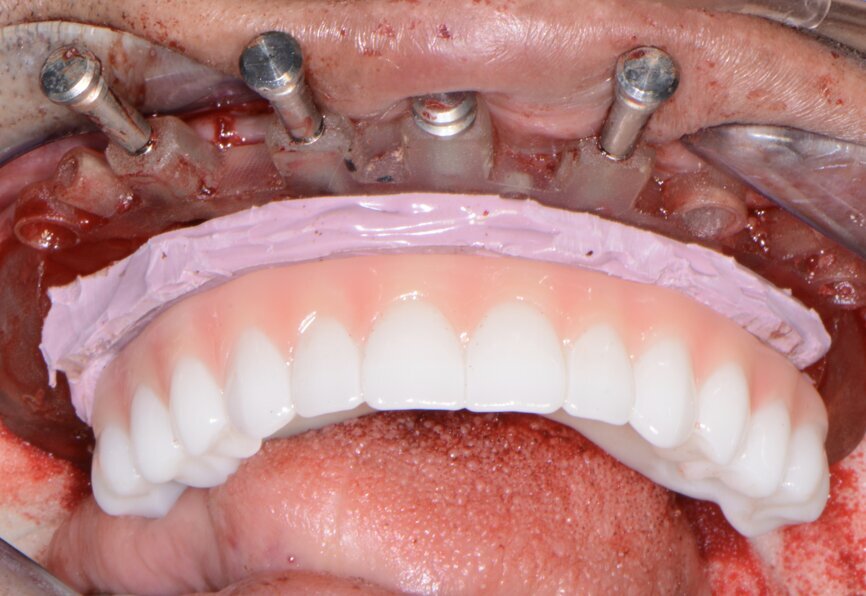

Fig. 15: Insertion of provisional restoration.

The prefabricated immediate provisional arch restorations (3DDX) with pre-drilled access openings were inspected before being tried in (Fig. 14). The maxillary provisional restoration was tried in to verify a passive fit over the temporary abutments. Once confirmed, a polyvinylsiloxane gasket was placed to avoid the restoration (Fig. 15) locking on during the relining procedure with Rebase II Fast hard reline material (Tokuyama Dental). After the material had polymerised, the immediate provisional restoration was removed and any access material removed with the Torque Plus (Aseptico) laboratory handpiece and an acrylic bur (Komet Dental).

Once trimmed and polished, the provisional arch restoration was seated and tightened with a torque wrench at 15 Ncm. The access openings were filled three-quarters of the way with PTFE tape, followed by Cavit (3M) filling material.

Seven days postoperatively, the patient returned with very little discomfort, swelling and bruising. He was very pleased with his new maxillary and mandibular fixed provisional restorations (Figs. 19 & 20). With the patient no longer anaesthetised, the occlusion was checked again to confirm there were no interferences in lateral and protrusive movements. The next step in his treatment would consist of full-arch impressions for the definitive restorations approximately four to five months postoperatively.